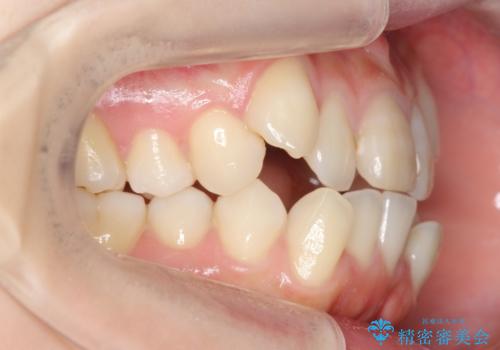

- 前歯のがたがたを主訴に来院。

八重歯と、前歯のやや開咬の症状もあり難易度としては中等度でした。